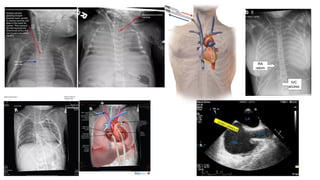

Types of cannulation vCentral cannulation vPeripheral cannulation vNeck vfemoral

Peripheral cannulation v Singlecannula v Two cannulae vNeck : Jagular and carotid vFemoral vein and femoral artery v